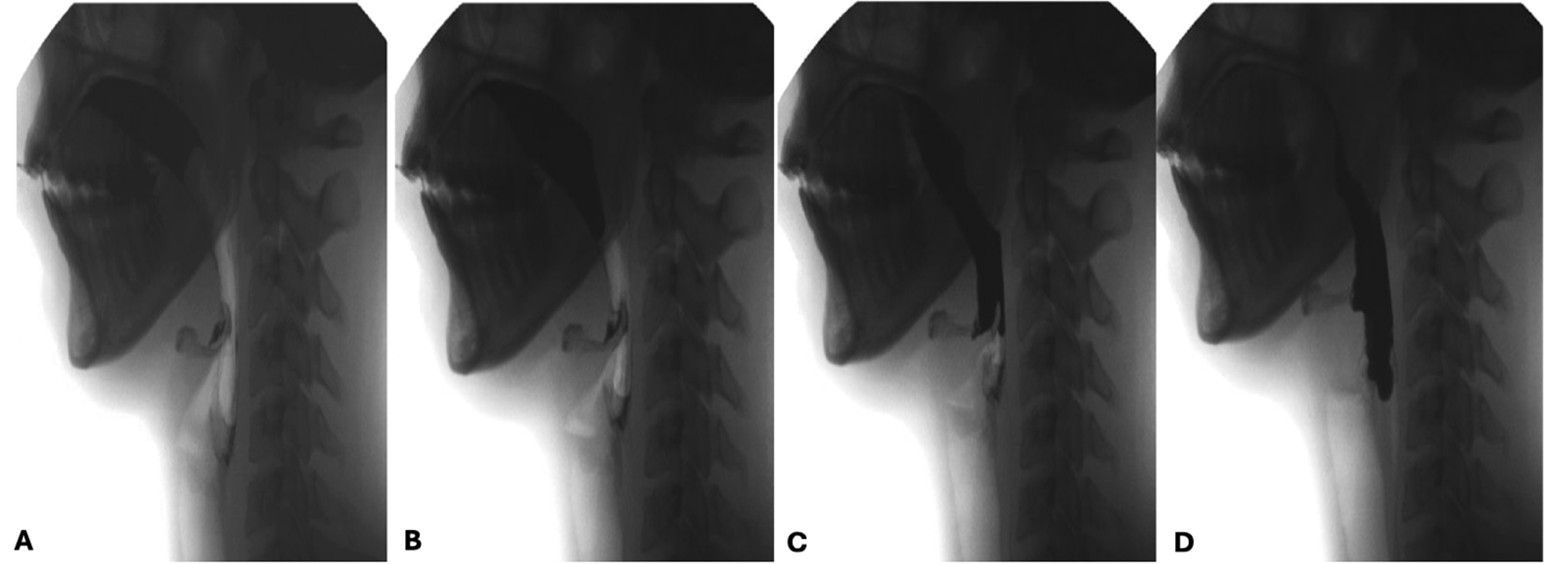

After the preparation of the boluses, voluntary transport to the pharynx occurs through coordinated movements: the tongue contracts, elevates anteriorly and depresses posteriorly, and the soft palate muscles relax, facilitating passage of the bolus through the fauces. This process usually lasts less than 1 second and the bolus is entirely propelled to the pharynx.

Bolus transport is most often impaired by reduced tongue strength, poor coordination of bolus movement and persistence of residue in the oral cavity, resulting in prolonged oral transit times. (Fig. 7)

Figure 7: Oral propulsive phase. Notice the tongue eversion and soft palate relaxation (A and B) with transfer of the bolus to the pharynx (C and D)